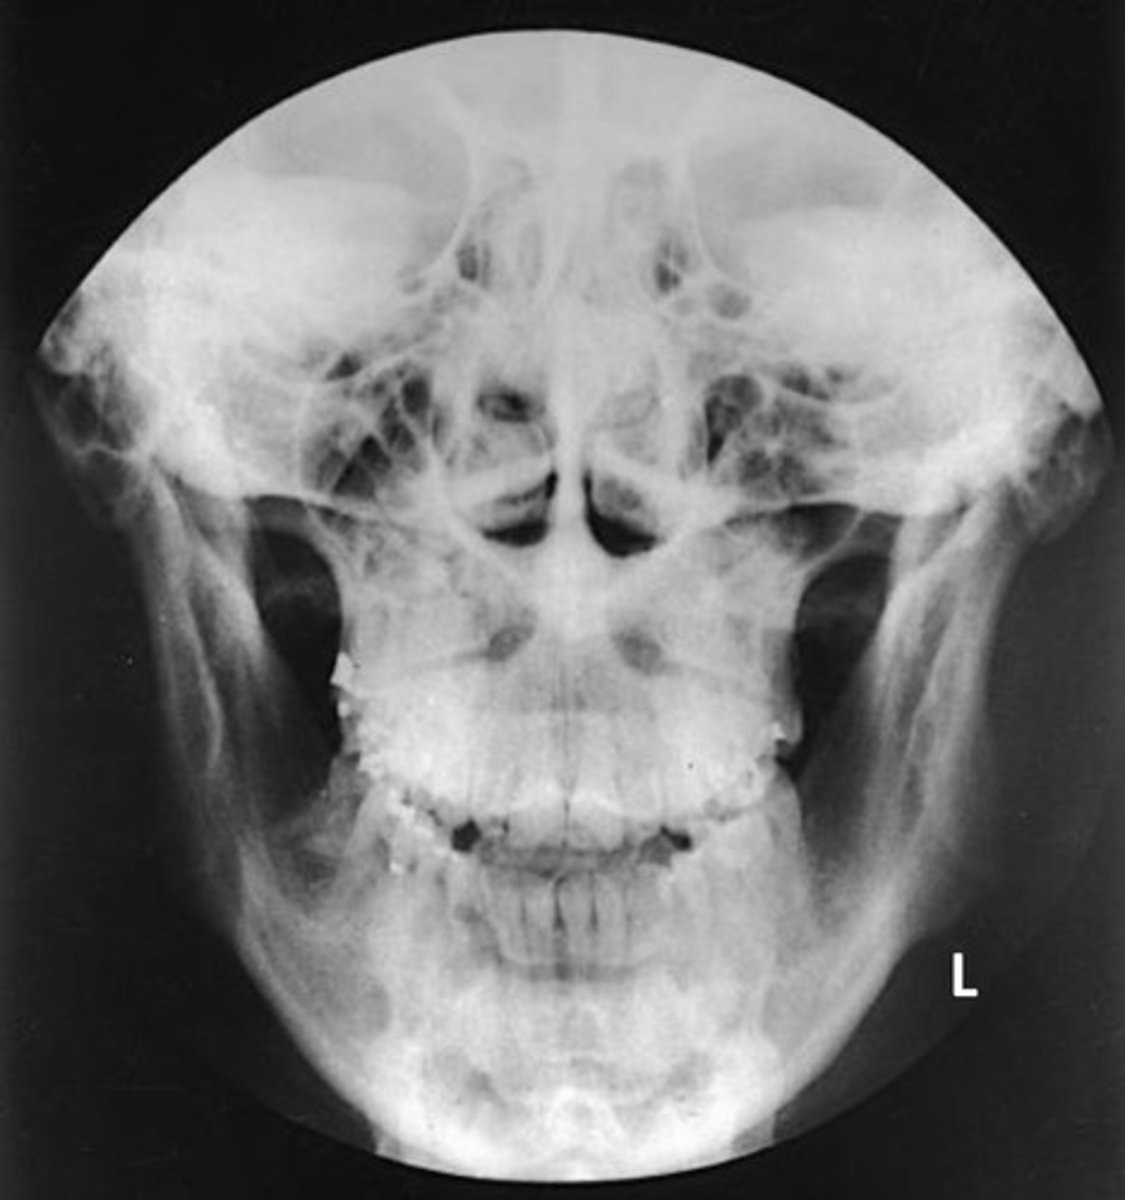

What projection and anatomy is demonstrated?

PA of the mandibular body